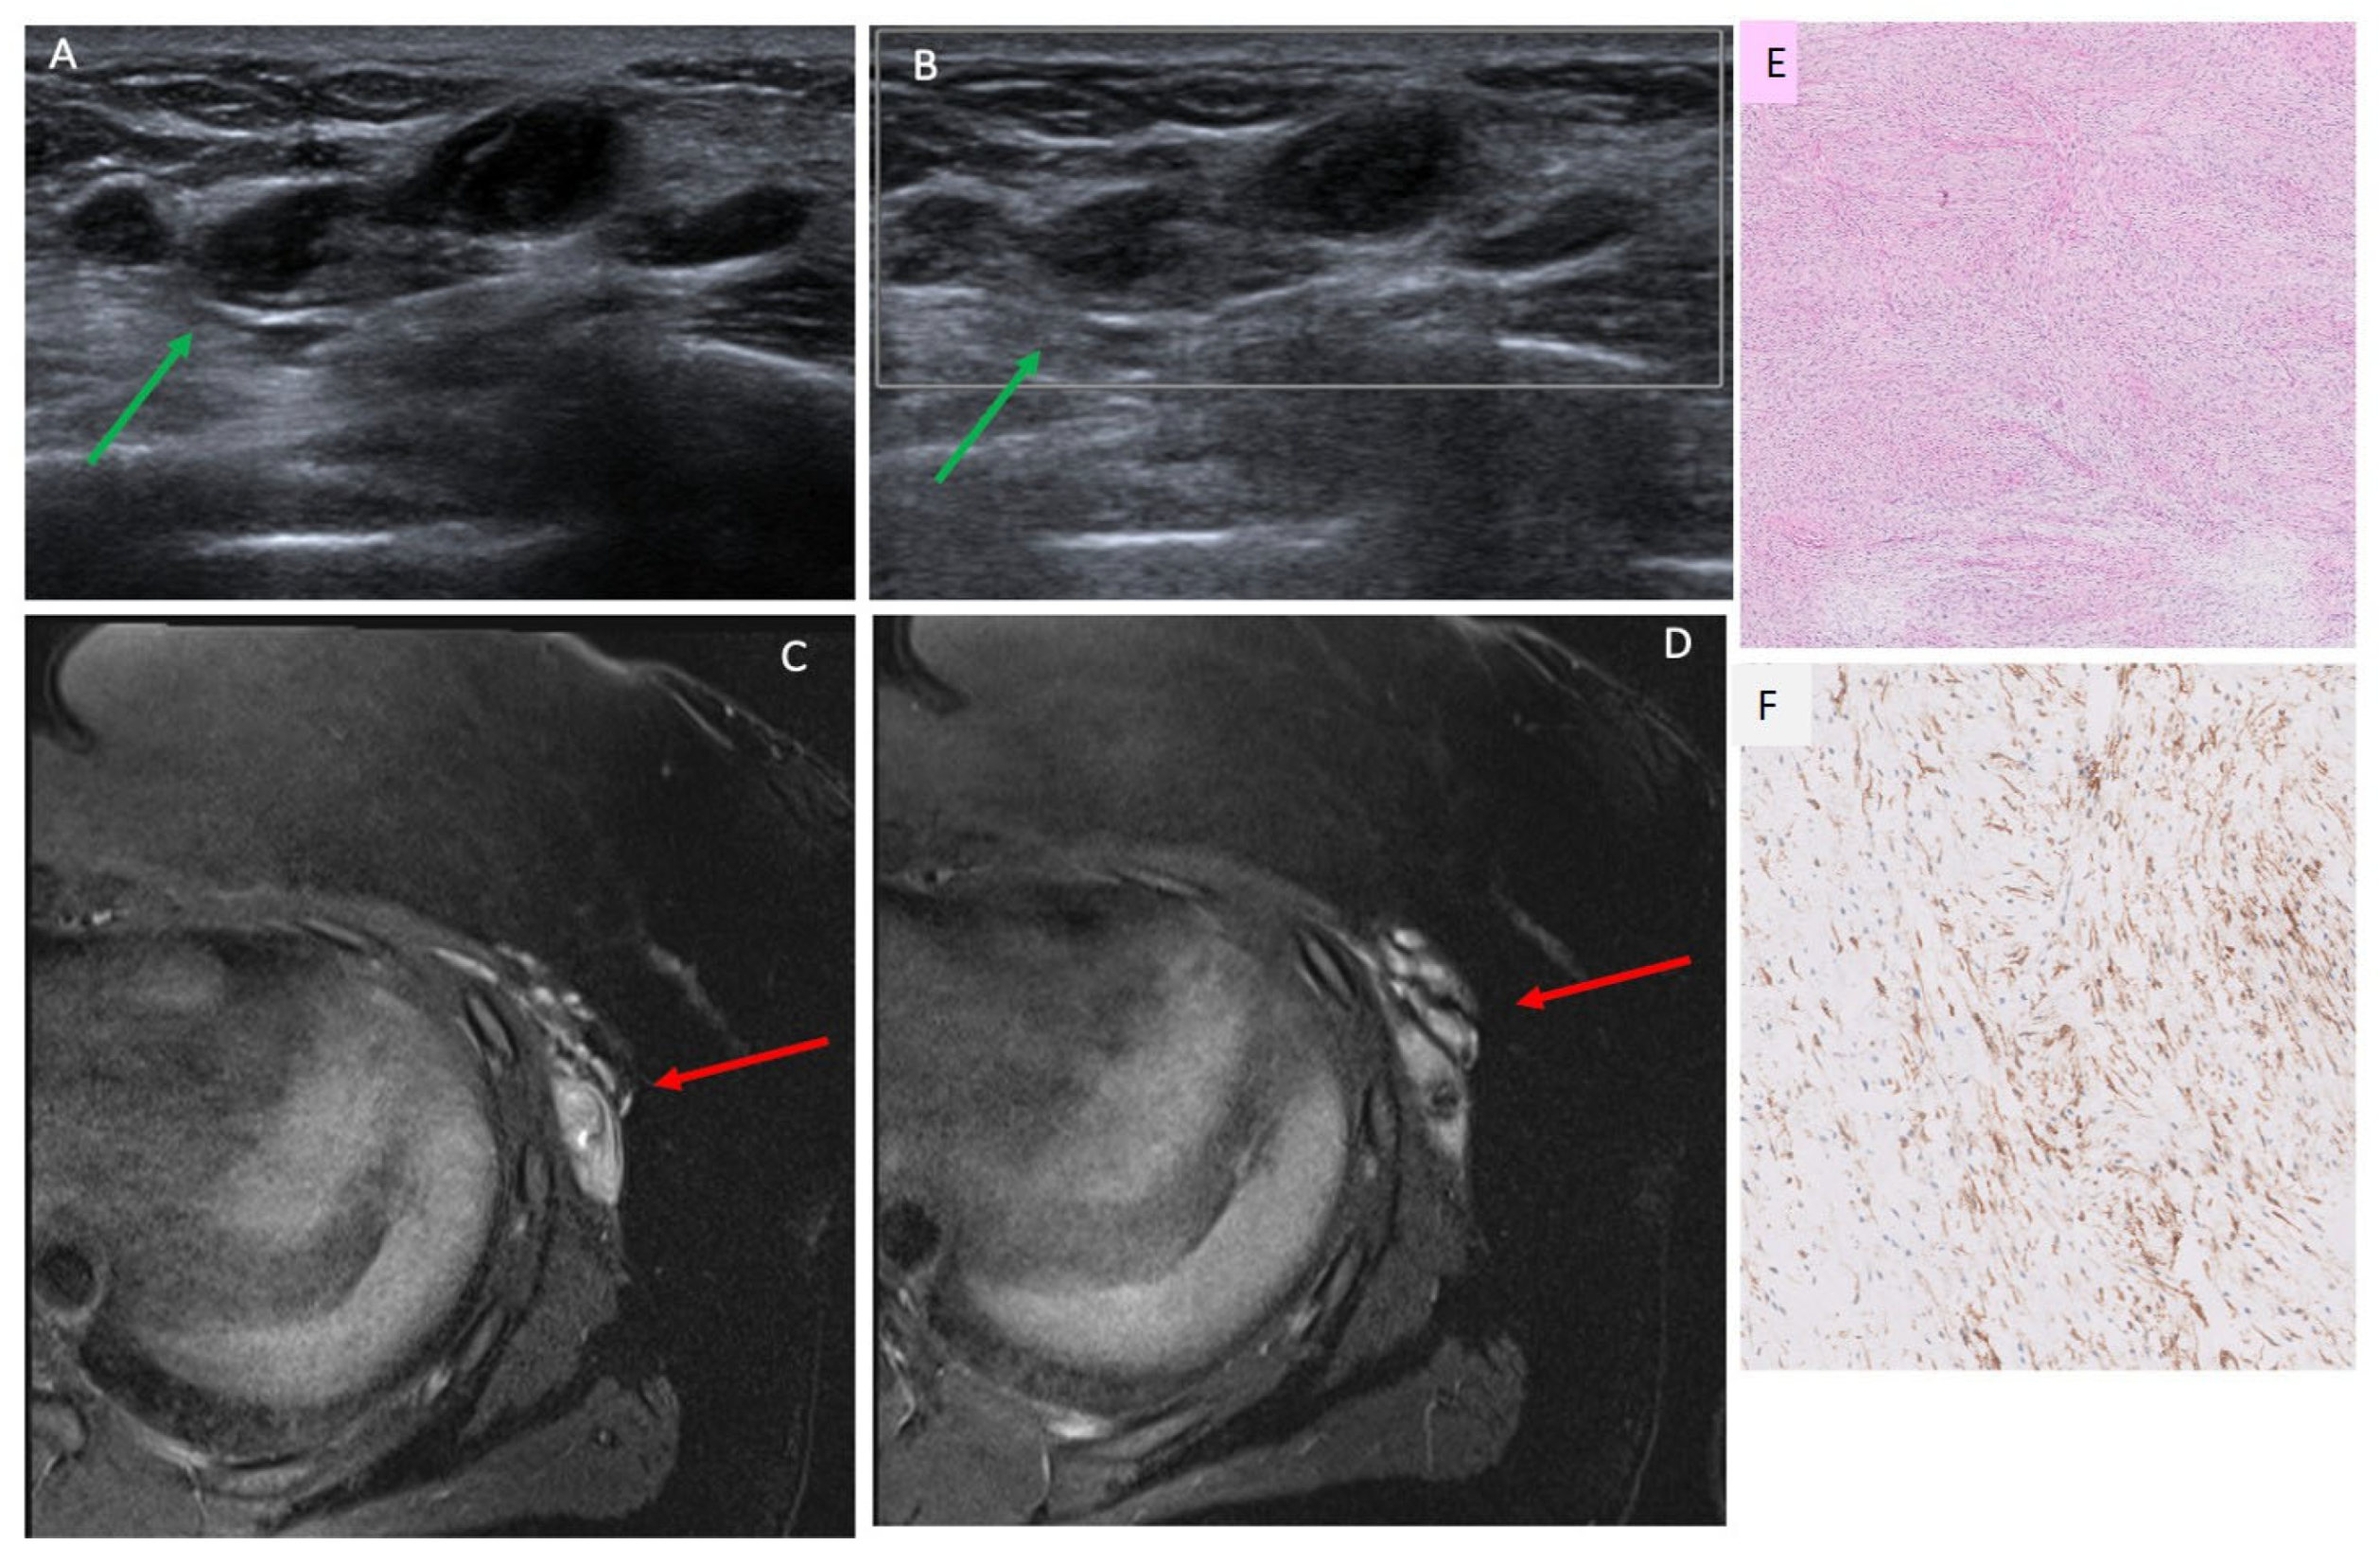

3.3. Ultrasound Findings

3.4. MRI Findings

3.5. AI Analysis